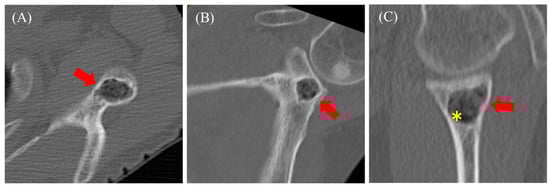

2.1. Case 1

2.2. Case 2